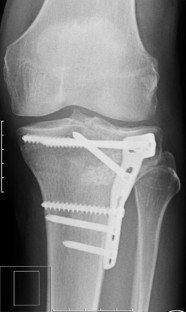

Abb. 2

This article reports on an innovative treatment concept to address split depression fractures (Schatzker type II) and depression fractures (Schatzker type III) of the tibial head using the balloon osteoplasty technique for fracture reduction.

Using the balloon technique a precise and safe fracture reduction can be achieved. This internal osteoplasty combines a minimally invasive percutaneous approach with a gentle raising of the depressed area and the associated protection of the regenerative layer below the articular cartilage surface. Fracture reduction by use of a tamper results in high peak forces over small areas, whereas by using the balloon the forces are distributed over a larger area causing less secondary stress to the cartilage tissue. This less invasive approach might help to achieve a better long-term outcome with decreased secondary osteoarthritis due to the precise and chondroprotective reduction technique.